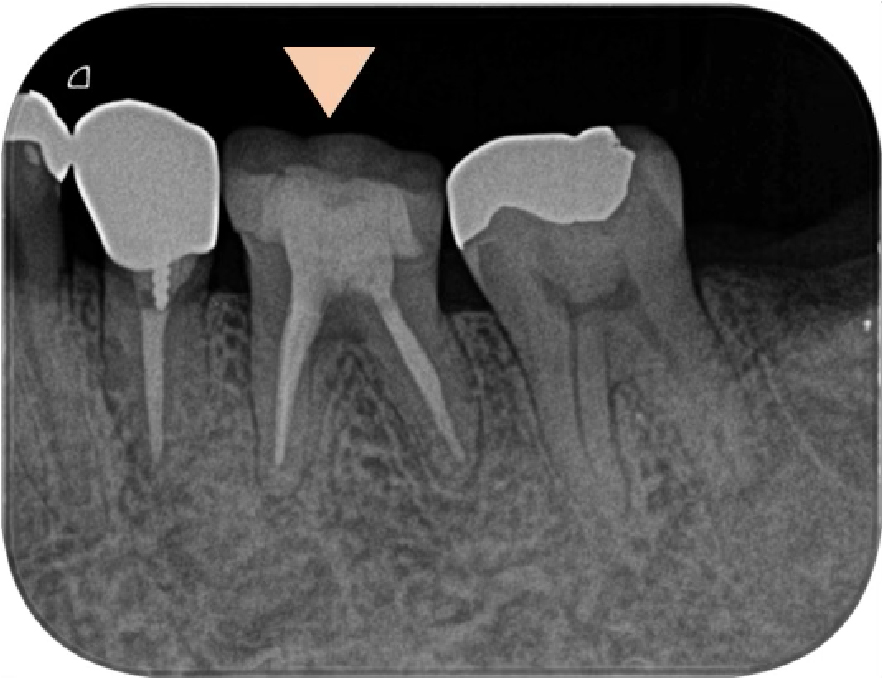

左下6番(第一大臼歯)のレントゲン所見にて、遠心根管周囲の顕著の骨吸収像が認められました(黄色点線)。

骨吸収の大きさとしてはやや大きく、さらに、口腔内を見ると歯肉の発赤腫脹を認め、歯周ポケットは11mmが入る状態でした(健康な歯肉の歯周ポケットは2-3mm)。

前医にて、この骨吸収の大きさとポケットの深さから、保存が不可能と診断されたことが推測されます。